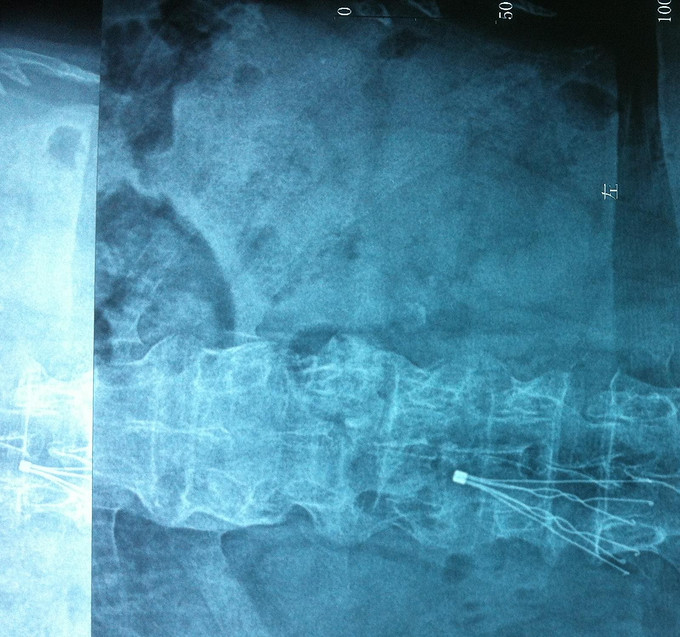

诊断:腰椎骨折 骨质疏松症 处理: 1、完善相关辅助检查,明确诊断,有无手术指证; 2、完善手术评估,有无手术禁忌,手术风险及并发症; 3、在局麻下行腰椎骨折椎体pkp术 4、术后给予全身抗骨质疏松治疗

随访 1、术后患者腰部疼痛明显减轻,术后第3日带支具下地活动,腰部轻度疼痛。 2、术后1个月,患者腰部无明显疼痛,腰部活动良好。 讨论:1、老年轻度外伤后出现腰痛,应行腰椎MR检查明确有无压缩性骨折? 2、老年骨质疏松骨质手术后是否常规抗骨质疏松治疗